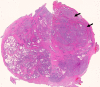

Purpose: To analyze the diffusion and perfusion parameters of central gland (CG) prostate cancer, stromal hyperplasia (SH), and glandular hyperplasia (GH) and to determine the role of these parameters in the differentiation of CG cancer from benign CG hyperplasia.

Materials and methods: In this institutional review board-approved (with waiver of informed consent), HIPAA-compliant study, 38 foci of carcinoma, 38 SH nodules, and 38 GH nodules in the CG were analyzed in 49 patients (26 with CG carcinoma) who underwent preoperative endorectal magnetic resonance (MR) imaging and radical prostatectomy. All carcinomas and hyperplastic foci on MR images were localized on the basis of histopathologic correlation. The apparent diffusion coefficient (ADC), the contrast agent transfer rate between blood and tissue (K(trans)), and extravascular extracellular fractional volume values for all carcinoma, SH, and GH foci were calculated. The mean, standard deviation, 95% confidence interval (CI), and range of each parameter were calculated. Receiver operating characteristic (ROC) and multivariate logistic regression analyses were performed for differentiation of CG cancer from SH and GH foci.

Results: The average ADCs (× 10(-3) mm(2)/sec) were 1.05 (95% CI: 0.97, 1.11), 1.27 (95% CI: 1.20, 1.33), and 1.73 (95% CI: 1.64, 1.83), respectively, in CG carcinoma, SH foci, and GH foci and differed significantly, yielding areas under the ROC curve (AUCs) of 0.99 and 0.78, respectively, for differentiation of carcinoma from GH and SH. Perfusion parameters were similar in CG carcinomas and SH foci, with K(trans) yielding the greatest AUCs (0.75 and 0.58, respectively). Adding K(trans) to ADC in ROC analysis to differentiate CG carcinoma from SH increased sensitivity from 38% to 57% at 90% specificity without noticeably increasing the AUC (0.79).

Conclusion: ADCs differ significantly between CG carcinoma, SH, and GH, and the use of them can improve the differentiation of CG cancer from SH and GH. Combining K(trans) with ADC can potentially improve the detection of CG cancer.